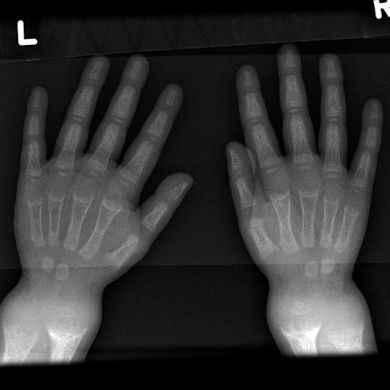

| X-ray of a two-year-old with rickets, with a marked bowing of the femurs and decreased bone density | |

تميل الأشعة السينية أو التصوير الشعاعي لمريض متقدم يعاني من الكساح إلى الظهور بطريقة كلاسيكية: الأرجل المنحنية (الانحناء الخارجي لعظم الساق الطويلة) والصدر المشوه. تحدث التغييرات في الجمجمة أيضًا مما يؤدي إلى ظهور "رأس مربع" مميز يُعرف باسم "caput quadratum".[15] تستمر هذه التشوهات في سن البلوغ إذا لم يتم علاجها تشمل العواقب طويلة المدى التقوس الدائم أو تشوه العظام الطويلة والظهر المنحني[16]

- يظهر التصوير الشعاعي عادة اتساع مناطق التكلس المؤقت للكراديس الثانوية للعظم غير المعدني. عادة ما تظهر التجلف ، والابلاء ، والتفلطح في الكراديس مع النمو وتحمل الوزن المستمر.[37] تُرى هذه التغييرات في الغالب في مواقع النمو السريع ، بما في ذلك عظم العضد القريب ، والزند البعيد ، وعظم الفخذ البعيدة وكل من الظنبوب الداني والبعيدة. لذلك ، يمكن إجراء مسح للهيكل العظمي للكساح باستخدام الصور الشعاعية الأمامية الخلفية للركبتين والمعصمين والكاحلين.[37]